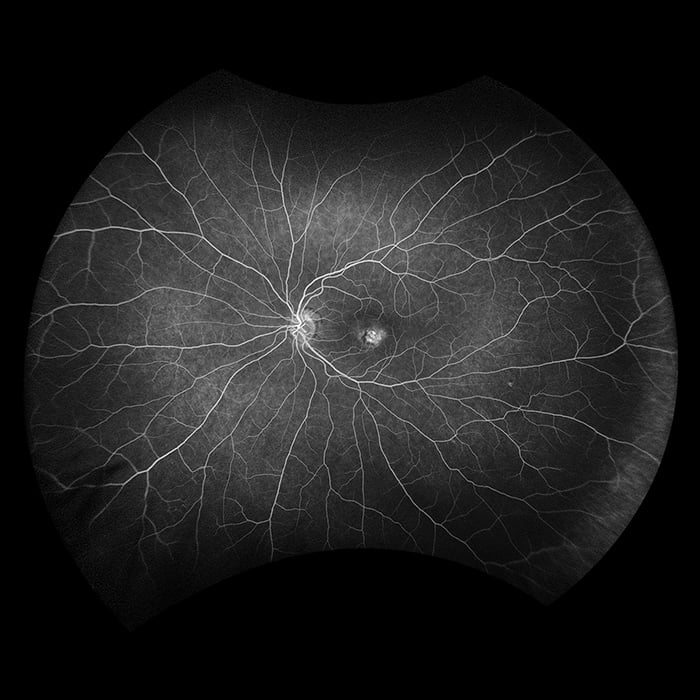

Silverstone RGB redéfinit l’excellence dans l’imagerie rétinienne. Seul équipement capable de produire des images optomap ultra grand champ à 200° en une seule prise, parfaitement intégrées à un OCT swept-source guidé. Pour la première fois, les professionnels de la vue ont accès à neuf modalités d'imagerie performantes dans un seul système, chacune étant conçue pour visualiser les pathologies où qu'elles se trouvent sur la rétine.

Il est démontré que l’optomap améliore la détection, la prise en charge des pathologies ainsi que le flux des patients. Maintenant disponible avec neuf modalités d’imagerie, y compris un OCT Swept-source intégré, Silverstone RGB facilite l'examen de la rétine du vitré jusqu’à l’interface choroïdo-sclérale.

- fa

- icg